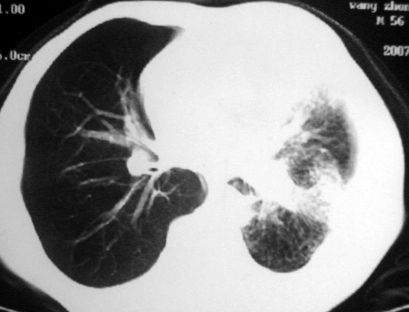

男,54岁,咳嗽,气喘半年,胸痛一月.

血性胸水

左侧胸腔积液 斜裂积液 心包积液 左肺不张 考虑左肺ca并胸膜心包转移。

支持左肺下叶中心型肺癌(累及舌叶)伴阻塞性肺炎、膨胀不全、胸腔积液、心包少量积液。

考虑左肺下叶中央型肺癌伴阻塞性肺炎及肺不张,纵隔受累可能,胸膜转移。